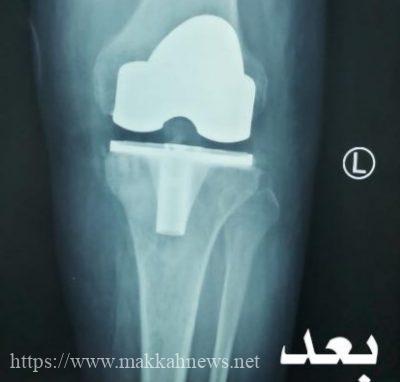

أجرى فريق متخصص في مستشفى محافظة وادي الدواسر العام جراحة ناجحة ومتقدمة لإستبدال مفصل ركبة بمفصل صناعي، وذلك لمريض كان يعاني من التهاب مزمن بالغشاء السينوڤى في مفصل الركبة اليسري مع خشونة متقدمة من الدرجة الرابعة مع عدم القدرة على المشي حيث تمكن الفريق بفضل الله من إستئصال الغشاء السينوڤى في الركبة كمرحلة أولى وإستبداله بمفصل صناعي في المرحلة الثانيةوقد بدأ المريض برنامجه المكثف من العلاج الطبيعي والمتابعة حتى تمكن من المشي ولله الحمد